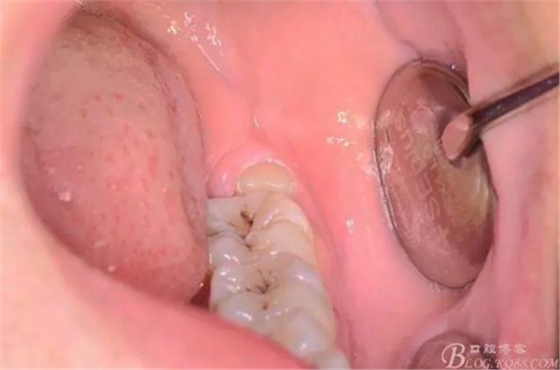

圖2.口內(nèi)可見黃豆大小大遠中面暴露,擬采用潛掘法分牙

分別取出牙冠、牙根,達到真正的微創(chuàng)拔牙